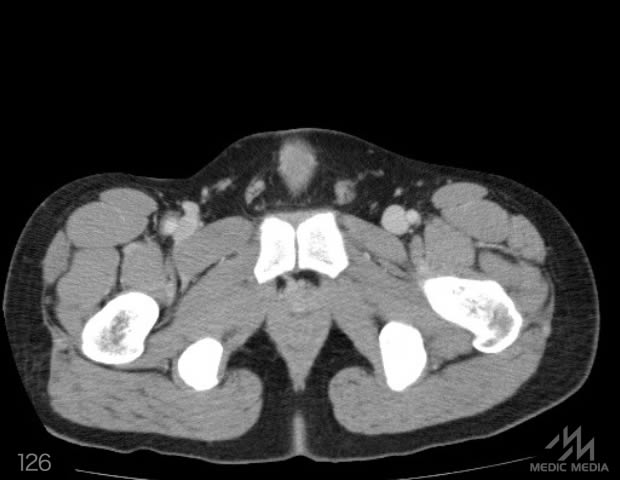

造影CT

消化器

肝区域